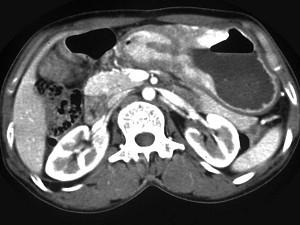

问题 女,56岁,上腹部钝痛、腹胀不适一月余,纳差、消瘦,影像检查如图,最可能的诊断是 ( )

选项 A、胃间质瘤 B、胃恶性间质瘤 C、胃腺癌并幽门狭窄 D、胃淋巴瘤 E、胃幽门管溃疡

答案 C